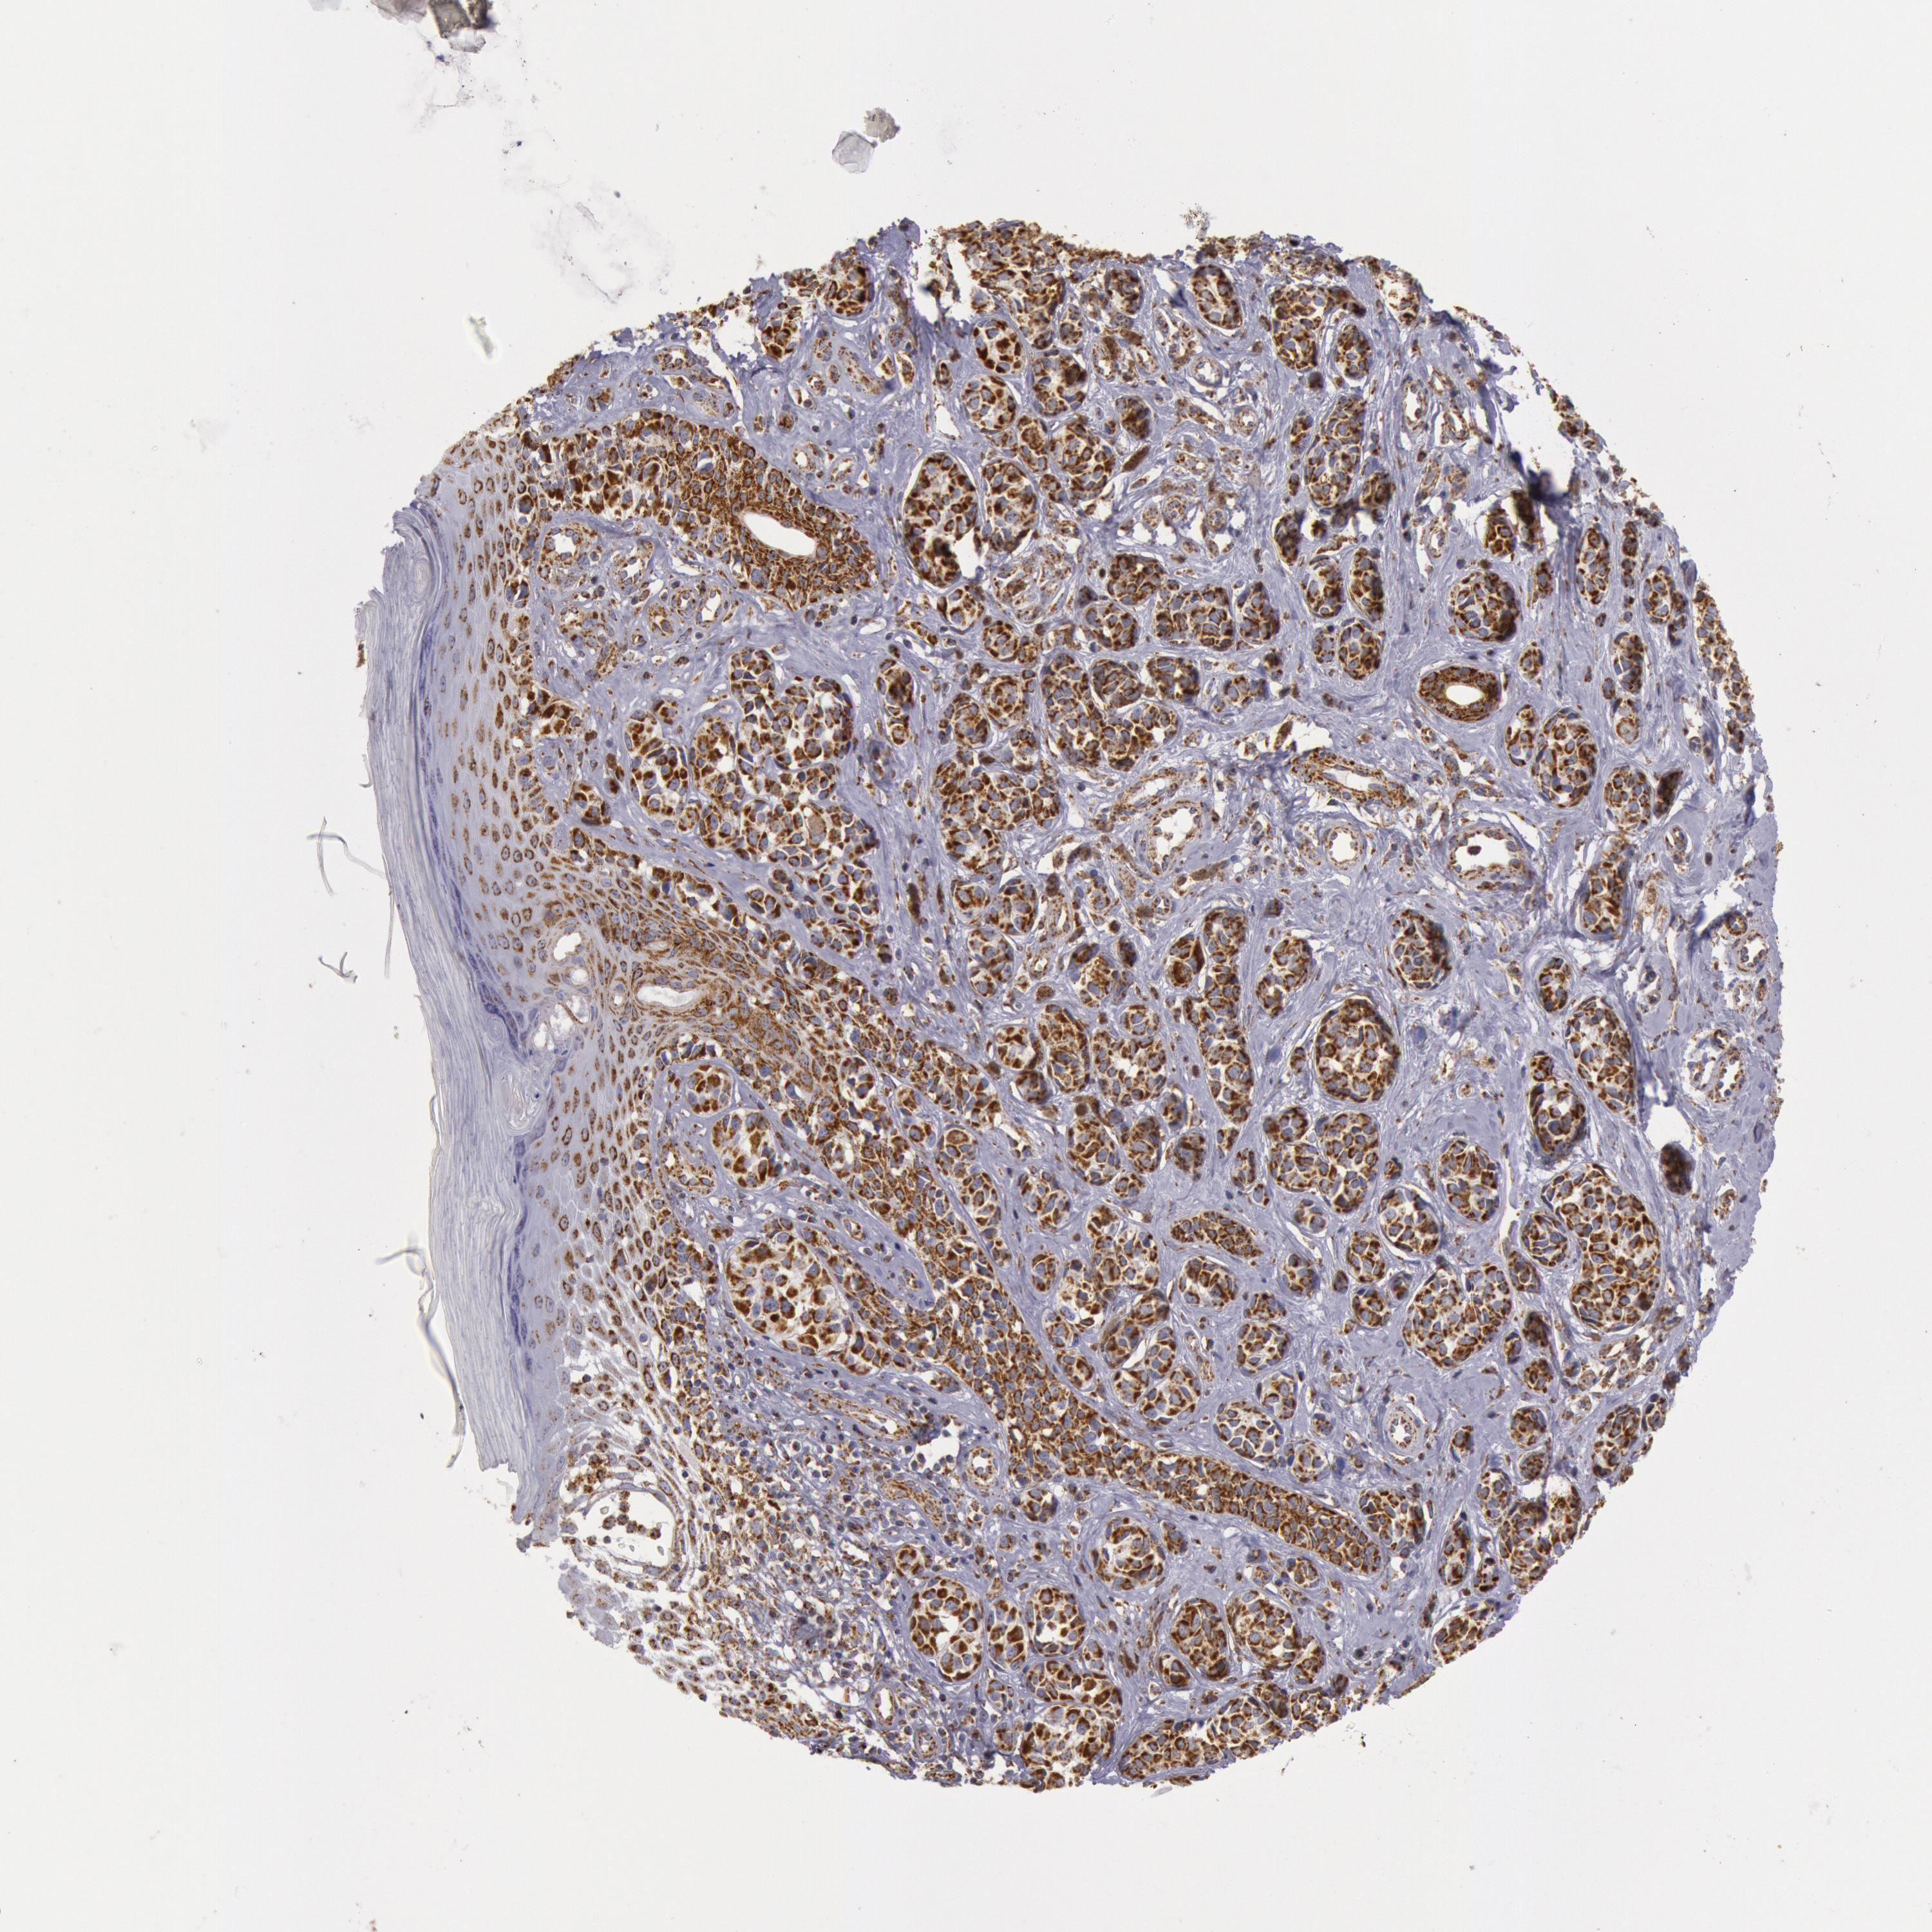

MELANOMA - Protein expressioni

A mouse-over function shows sample information and annotation data. Click on an image to view it in a full screen mode. Samples can be filtered based on level of antibody staining by selecting one or several of the following categories: high, medium, low and not detected. The assay and annotation is described here.

Note that samples used for immunohistochemistry by the Human Protein Atlas do not correspond to samples in the TCGA dataset.

Antibody stainingi

Antibody staining in the annotated cell types in the current human tissue is reported as not detected, low, medium, or high, based on conventional immunohistochemistry profiling in selected tissues. This score is based on the combination of the staining intensity and fraction of stained cells.

Each image is clickable and will lead to virtual microscopy that enables deeper exploration of all samples and also displays staining intensity scores, fraction scores and subcellular localization as well as patient and tissue information for each sample.

Antibody HPA001247

Staining

High

Medium

Low

Not detected

Intensity

Strong

Moderate

Weak

Negative

Quantity

>75%

75%-25%

<25%

None

Location

Nuclear

Cytoplasmic/membranous

Cytoplasmic/membranous,nuclear

Malignant melanoma, NOS